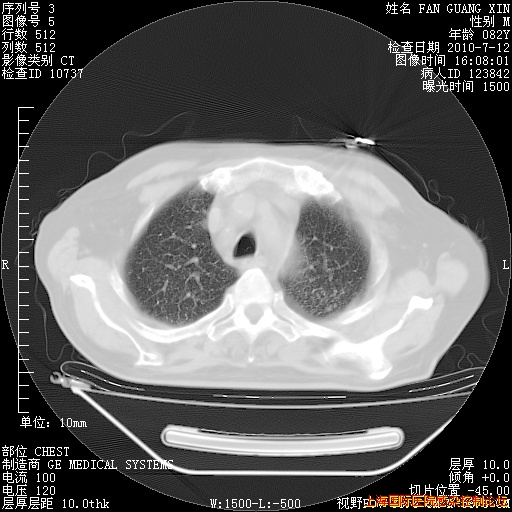

补发6月12日肺部CT肺窗

6月12日肺窗

6月12日纵膈窗